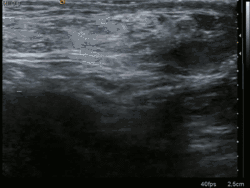

Medical imaging

A physician may diagnose an inguinal hernia, as well as the type, from medical history and physical examination.[20] For confirmation or in uncertain cases, medical ultrasonography is the first choice of imaging, because it can both detect the hernia and evaluate its changes with for example pressure, standing and Valsalva maneuver.[21]

When assessed by ultrasound or cross sectional imaging with CT or MRI, the major differential in diagnosing indirect inguinal hernias is differentiation from spermatic cord lipomas, as both can contain only fat and extend along the inguinal canal into the scrotum.[22]